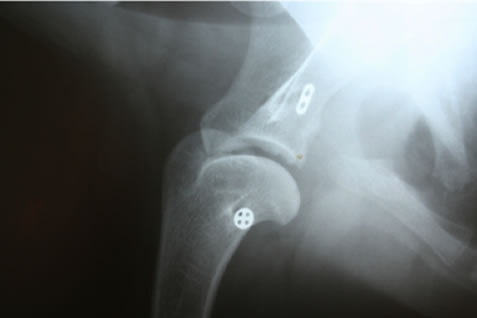

手根関節

手根関節脱臼 / 亜脱臼 / 不安定症 / 過伸展

症状:前足がオットセイのような形になる、手首が床に着く、前足の跛行、手首の関節の腫れや痛み

手根関節脱臼 / 亜脱臼 / 不安定症 / 過伸展とは

落下やジャンプに伴って起こる靭帯損傷や、免疫介在性関節炎、糖尿病、クッシングなど内科疾患に関連して起こる靭帯変性により生じる手根関節の不安定性

診断

レントゲン検査など

治療

外科適応の場合は全関節固定術、部分関節固定術、スーチャーアンカー法などをおこない、手根関節を固定します